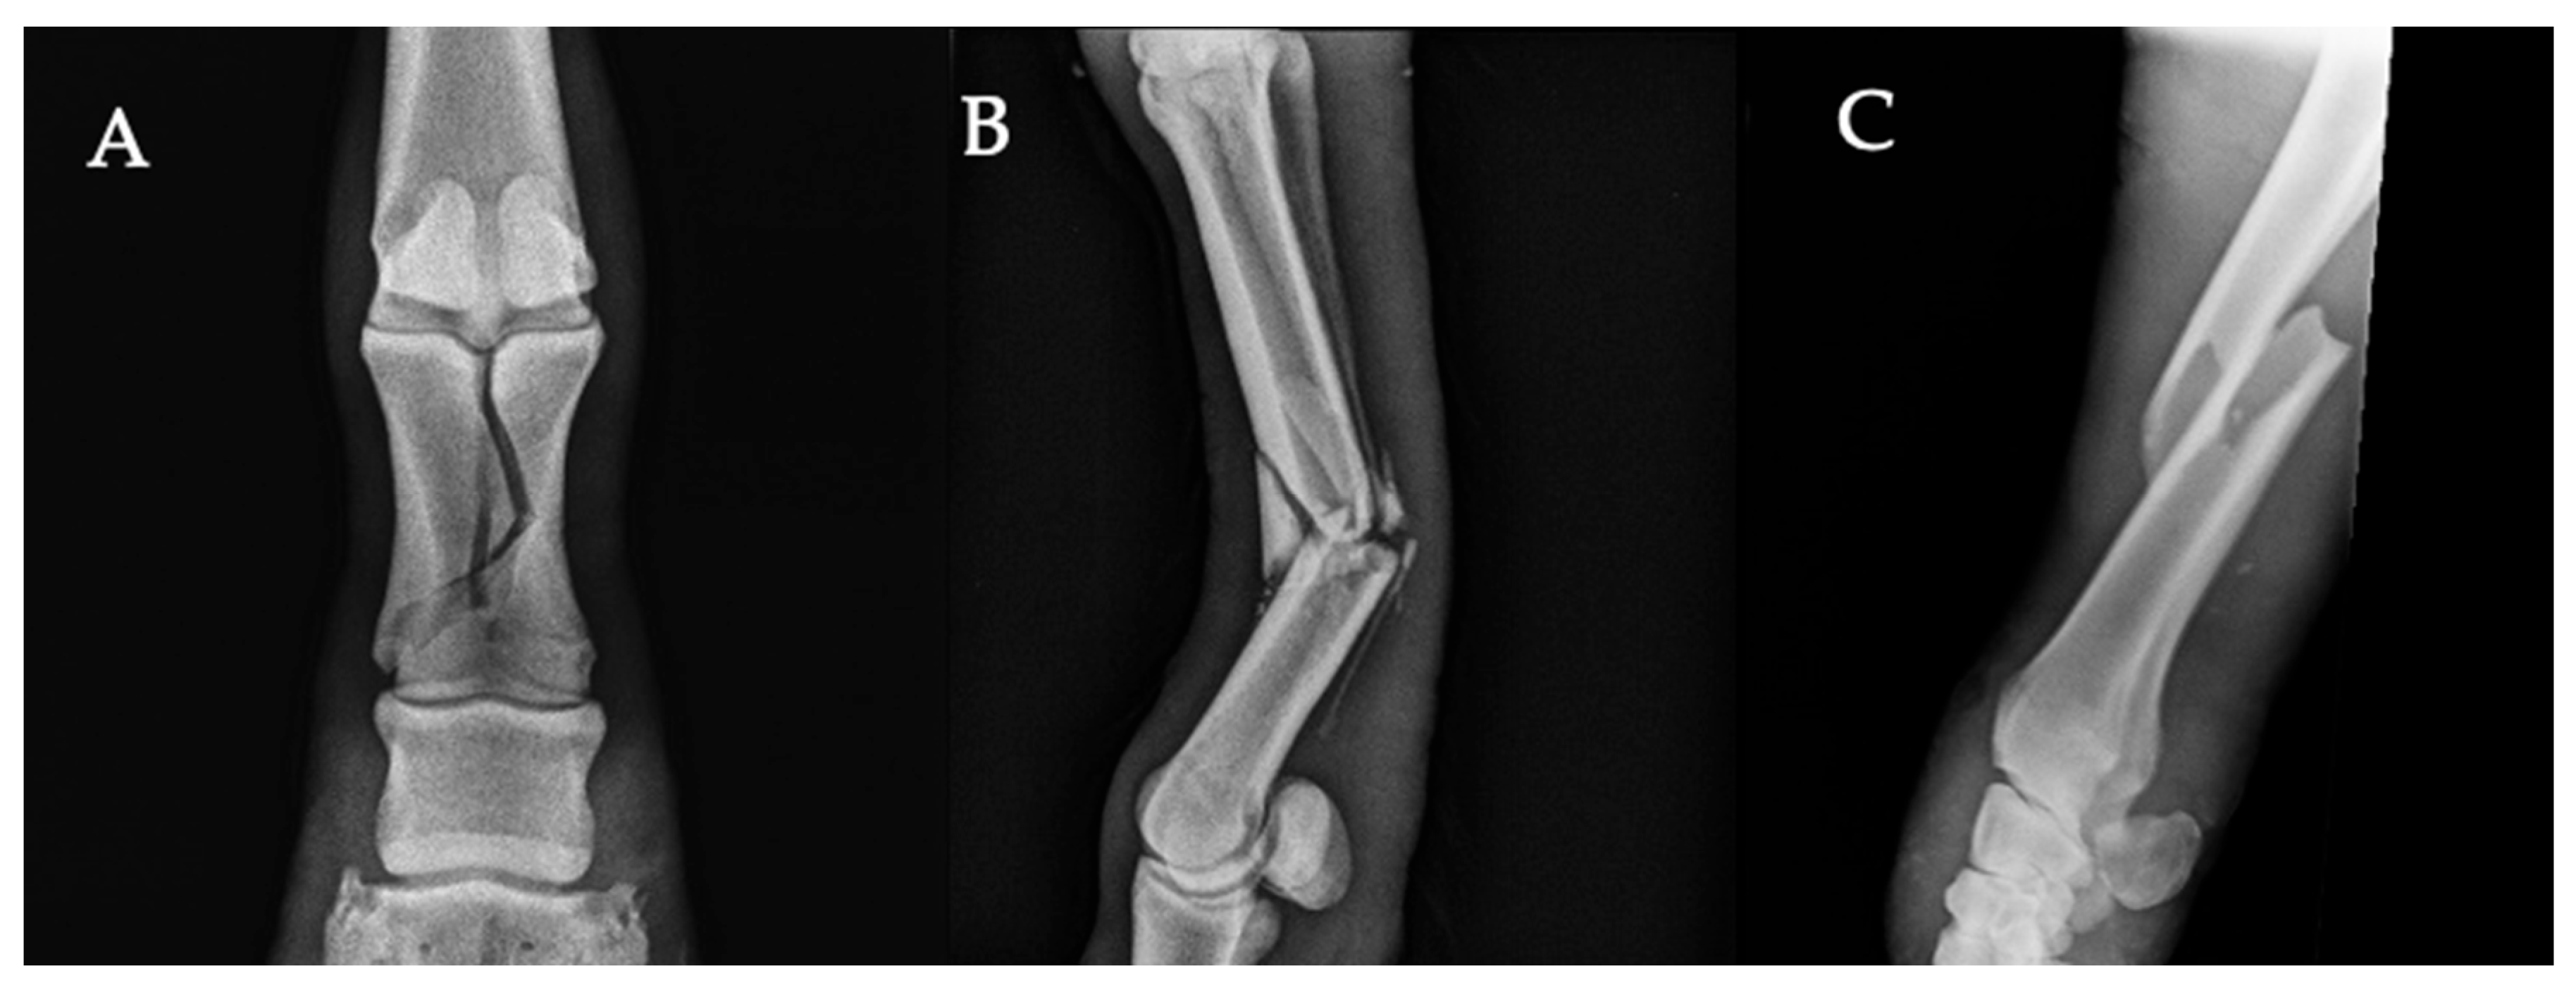

- Fractures. Defined as visible discontinuity of the cortical bone or fragmentation of osseous structures, regardless of anatomical location or orientation.

- Periosteal new bone formation. All forms of periosteal new bone formation (smooth, irregular, multilamellar, or extensive) were grouped under a single category.

- Angular limb deformities. Defined as varus or valgus deviations in the frontal plane, confirmed radiographically by misalignment of the limb axis and asymmetry of the physis or metaphysis on dorsopalmar/dorsoplantar views.